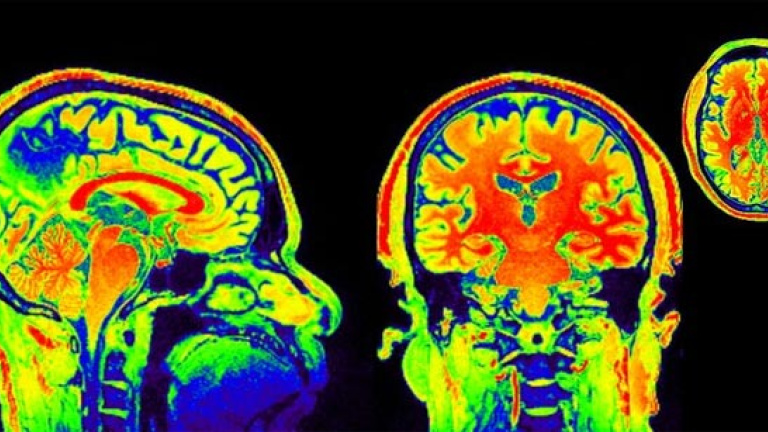

Los investigadores han intentado utilizar técnicas de imagen para verlo, y sí que han encontrado indicios de cambios cerebrales

Los investigadores han intentado utilizar técnicas de imagen para verlo, y sí que han encontrado indicios de cambios cerebrales. Los individuos deprimidos a menudo tiene una actividad exagerada en la amígdala (parte del cerebro implicada en el proceso de las emociones) que no es controlada adecuadamente por la corteza prefrontal, responsable de tareas mentales complejas. Los antidepresivos, piensan algunos investigadores, aquietan la actividad de la amígdala, mientras que la TCC aumenta la actividad y, por tanto, la capacidad de control de la corteza prefrontal. Los escasos estudios existentes indican que se producen cambios cerebrales tras una terapia cognitiva de 14 semanas de duración, pero no son concluyentes y tampoco se sabe si son la causa o una consecuencia de la mejora del paciente. Lo que sí parece es que los cambios son perdurables.